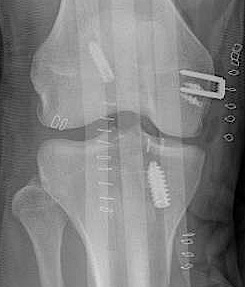

3. Reconstruction of MCL and posteromedial corner

A. Single bundle anatomic allograft MCL reconstruction (no POL)

ACL / MCL

Marx technique MCL reconstruction with tendoachilles allograft PDF

Marx technique MCL reconstruction with tendoachilles allograft Vumedi

Femoral attachment

- 4 mm proximal and posterior to medial epicondyle

- image intensifier: intersection of the posterior femoral condyle with Blumensaat's line

- 40o anterior to avoid notch

- 40o proximal to avoid PCL tunnel

Tibial attachment

- 6 cm from joint line

- just posterior to pes attachment

B. Single bundle anatomic hamstring autograft MCL reconstruction (no POL)

LaPrade surgical technique PDF

C. Double bundle anatomic reconstruction of MCL and POL